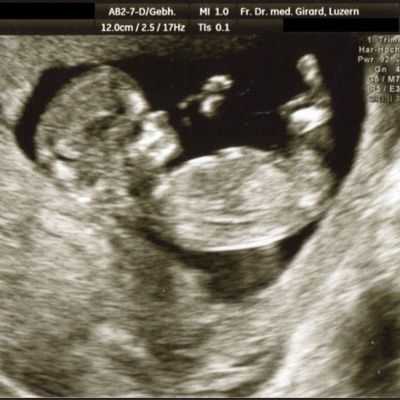

Der Ultraschall hilft uns dabei als einzige Methode, das ungeborene Kind in der Gebärmutter direkt sichtbar zu machen.

können das Wachstum des Kindes und die Fruchtwasser-Menge, wichtige Hinweise auf eine normale Entwicklung des Kindes, beurteilt werden. In diesem Alter können auch schwerere Fehlbildungen erfasst werden, beispielsweise von Kopf und Gehirn, Wirbelsäule, Herz, Nieren, Magen und Extremitäten. Ebenso wird der Sitz der Plazenta beurteilt.